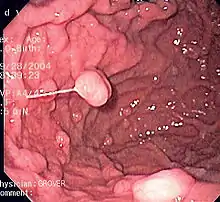

Clinical significance

Diseases

A series of radiographs can be used to examine the stomach for various disorders. This will often include the use of a barium swallow. Another method of examination of the stomach, is the use of an endoscope. A gastric emptying study is considered the gold standard to assess the gastric emptying rate.[44]

A large number of studies have indicated that most cases of peptic ulcers, and gastritis, in humans are caused by Helicobacter pylori infection, and an association has been seen with the development of stomach cancer.[45]